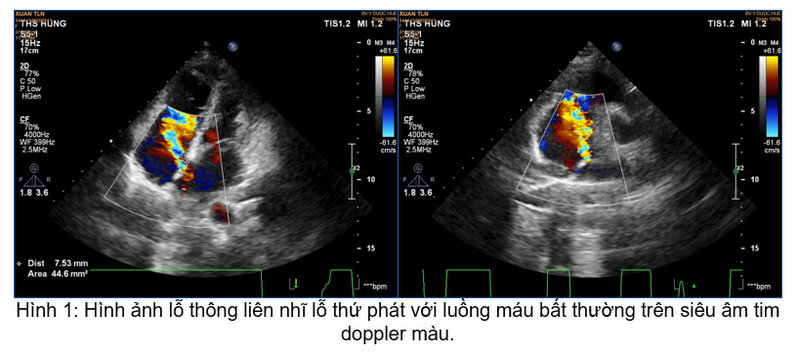

- Thông liên nhĩ

Siêu âm tim cơ bản giúp phát hiện bệnh lý thông liên nhĩ- Hẹp eo động mạch chủ